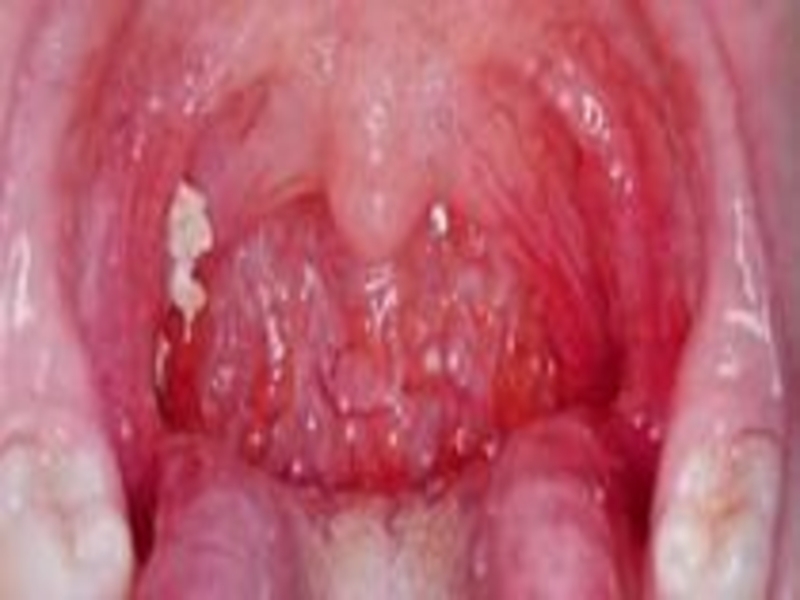

Токсическая форма дифтерии начинается остро, с появления резкого увеличения

миндалин язычка, мягкого неба. отечность мягких тканей зева может быть

настолько резко. что миндалины соприкасаются друг с другом, отодвигая назад язычок. голос приобретает носовой оттенок, возникает неприятный запах изо рта. Налеты на миндалинах грязно-белые. Регионарные лимфоузлы резко увеличены. Отмечается отечность окружающей клетчатки.

Различают 1, 2,3 степень токсической дифтерии зева.

При 1 степени отек до середины шеи.

При 2 степени до ключицы.

При 3 степени ниже ключицы.

Обычно состояние тяжелое, Т-40, выражена слабость.